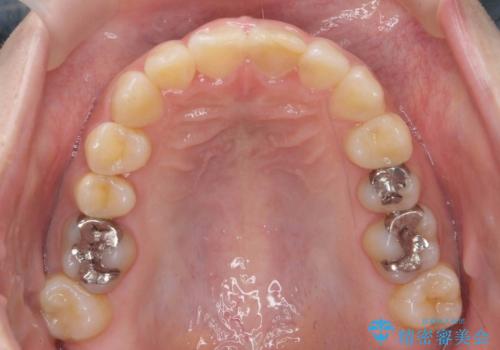

前歯のがたつき ガミースマイルの改善

- 前歯のがたつきとガミースマイルの改善を希望して来院。

ガミーは非常に軽度でひどくはなかったのですが、改善を強く希望されていました。

上の前歯をひっぱりあげて目立たなくするために、上の前歯のワイヤー部分矯正を行い、ミニスクリューからわずかに引っ張り上げました。

また、右上の犬歯の反対咬合についてもワイヤー矯正で短期間で改善することができました。

前歯の過蓋咬合についても改善しています。

- 110万円(ワイヤー部分矯正 ミニスクリュー 16.5万円、全顎インビザライン 93.5万円)費用は治療当時の料金となります